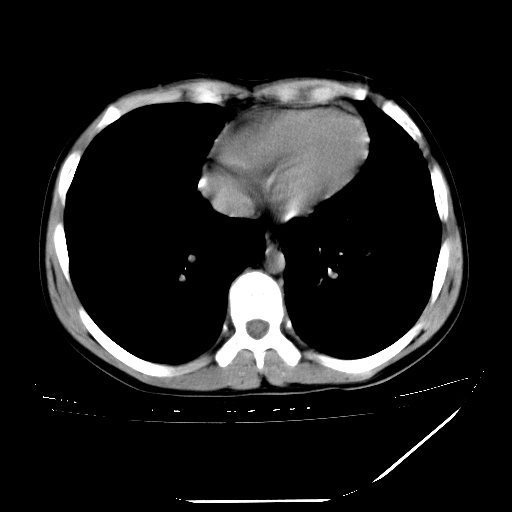

男,13岁,咳嗽、咳痰伴发热一周。

中上纵隔见多枚淋巴结肿大,部分相互融合成团片,左肺门增大,上叶支气管变窄,肺内多处斑片状 索条状及棉絮状致密影。临床“男,13岁,咳嗽、咳痰伴发热一周。”首先考虑:原发综合征!不除外淋巴瘤可能!

纵隔多发肿大淋巴结,部份有融合改变。双肺血管气管束增厚,以肺门为中心向外周散发,以左肺下叶为明显。考虑淋巴瘤可能性大。不除外原发综合征。

中上纵隔见多枚淋巴结肿大,部分相互融合成团片,左肺门增大,上叶支气管变窄,左肺支气管血管束增粗,可见磨玻璃样影。临床“男,13岁,咳嗽、咳痰伴发热一周。”首先考虑:淋巴瘤可能性大!

中上纵隔见多枚淋巴结肿大,部分相互融合成团片,纵隔内脂肪间隙模糊,左肺门增大,上叶支气管变窄,左肺支气管血管束增粗,可见磨玻璃样影。考虑纵隔淋巴管炎